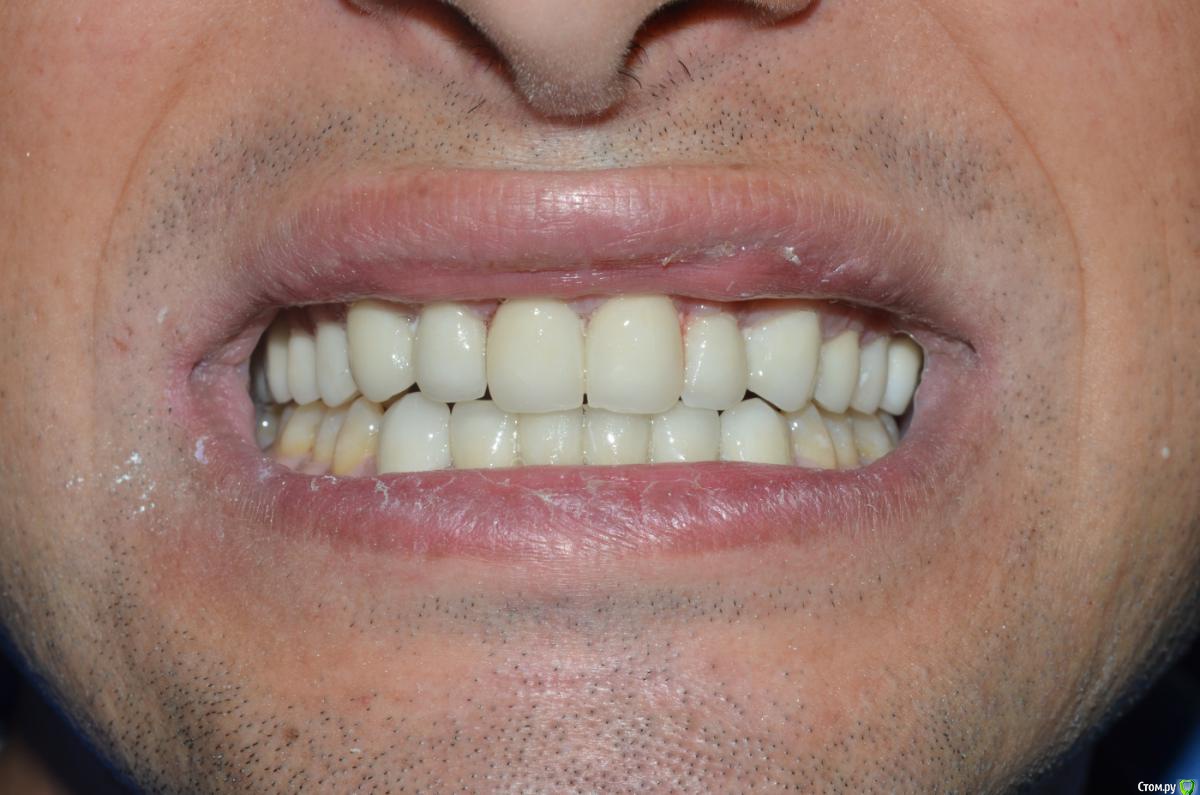

NazranDantist Опубликовано 4 сентября, 2015 Поделиться Опубликовано 4 сентября, 2015 К сожалению фото до где-то потерялись, были очень длинные клыки, смыкались по типу ножниц. Пришлось поднимать прикус на 0.6-0.8 мм. Обточка, времянки, слепки - 3 часа, фиксация 2 часа, без примерок на готово. Пациент попросил "ахпер, сделай две белый полосы, как на моем камаро" . Все циркон с вестибулярной облицовкой, фиксация Фуджи+. Фоткал пока цемент еще застывал.Учимся работать по китайскому протоколу, тотал за неделю и за 3000$ 1 1 Ссылка на комментарий

NazranDantist Опубликовано 4 сентября, 2015 Автор Поделиться Опубликовано 4 сентября, 2015 (изменено) Техник сделал все за 3 дня, сроки поджимали, к тому же пациент не требовал особых изысков и соответственно платил, главное белые и ровные))) Фото в первом сообщении немного засвечено. Цемент не убран на фото, через месяц приедет, еще раз сфоткаю с десной. Модели, слепки не фотографировал, был классический оттиск двухслойный с-силиконом. Кризис)) Изменено 4 сентября, 2015 пользователем NazranDantist Ссылка на комментарий

NazranDantist Опубликовано 4 сентября, 2015 Автор Поделиться Опубликовано 4 сентября, 2015 Почему центральные резцы желтее остальных(нижние тоже)?Одним нельзя было сделать?Форма клыков меня смущает..И почему то мне кажется что при латеротрузии контакт у вас не только на клыках есть но и на двойках..Циркон наверное от вспышки светит, в полости рта все одного цвета, А-1, вспышка стандартная. Движения на клыках и премолярах, здесь не стандартое расположение клыков и двоек, обратите внимание на расстояние между этими зубами. Ссылка на комментарий

NazranDantist Опубликовано 4 сентября, 2015 Автор Поделиться Опубликовано 4 сентября, 2015 Пациенту понравилось. Эстетика не супер, я ж говорю, делалось за три дня и за ограниченный бюджет, в 18:00 - достали из печки после глазури, в 21:00 пациент уехал (час на транспортировку работы), еще не дорос до того уровня, чтоб выбирать пациентов . С десной все ок, фото препа - перед фиксацией (можете обратить внимание на десну), фото после - только, только цемент начал стыть. Перед этой работой читал про то, как наши граждане ездят в китай лечить зубы, и все думал, как это за 3-5 дней там делают тоталы. Теперь я это знаю . 1 Ссылка на комментарий